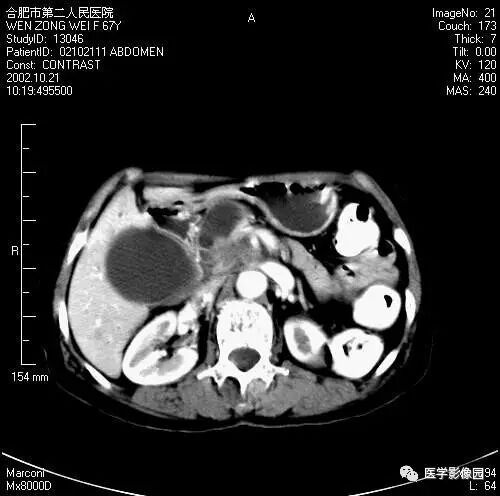

A

B

图6-4-20胰腺癌

A. 增强扫描见肝门部转移性淋巴肿(↑),

肝动脉部分被包绕(长↑),

可见大量腹水;

B.胰头部不规则分叶状增大,

胰体、尾部萎缩,

主胰管局限性扩张(↑),胆囊明显增大